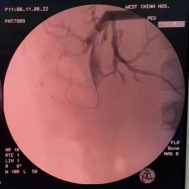

考虑患儿肝移植手术腹腔粘连紧密及局部解剖位置改变,开腹手术难度较大。多学科团队多次进行会诊讨论,最后决定先行经皮肝穿刺胆道引流(PTCD)减轻炎症及黄疸,术中同时取肝脏活检进一步明确诊断。患儿术后胆汁引流通畅,肝功恢复正常。待原吻合口炎症水肿消退及经皮穿刺隧道稳定后,患儿于6月1日在全麻下行胆道镜取石,取石完成后术中胆道造影可见造影剂通过胆肠吻合口,继续放置T管引流,1个月后经T管造影提示肝内外胆管通畅,造影剂可进入肠腔。随后,患儿于8月11日在全麻下行经皮胆道镜检查,经原PTCD皮肤窦道置入胆管镜,在胆道镜直视下导丝引导置入4mm球囊扩张器反复扩张原胆肠吻合口(图2-4),扩张完成后胆道镜可轻松通过胆肠吻合口进入空肠,造影显示吻合口通畅(图5),放置适当直径引流管支撑引流,术后患儿无特殊不适。

图5:扩张后造影剂进入肠腔顺利